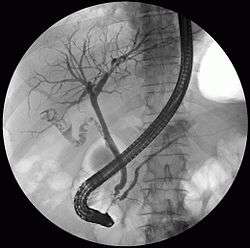

ERCP image showing the biliary tree and the main pancreatic duct.